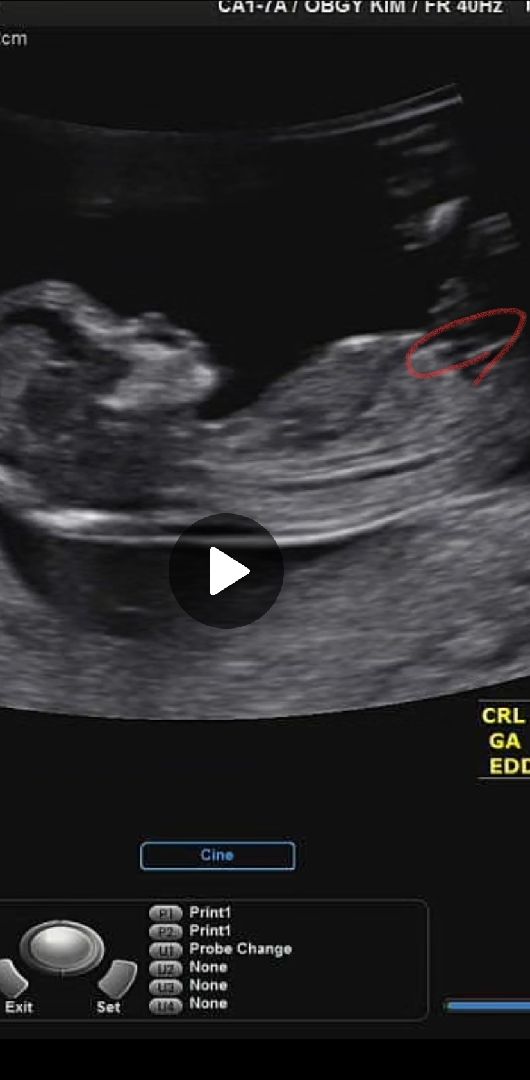

1차기영아검사에요 동영상보다가 캡쳐했습니다 지금은 13주4일? 쉬싼건가여?